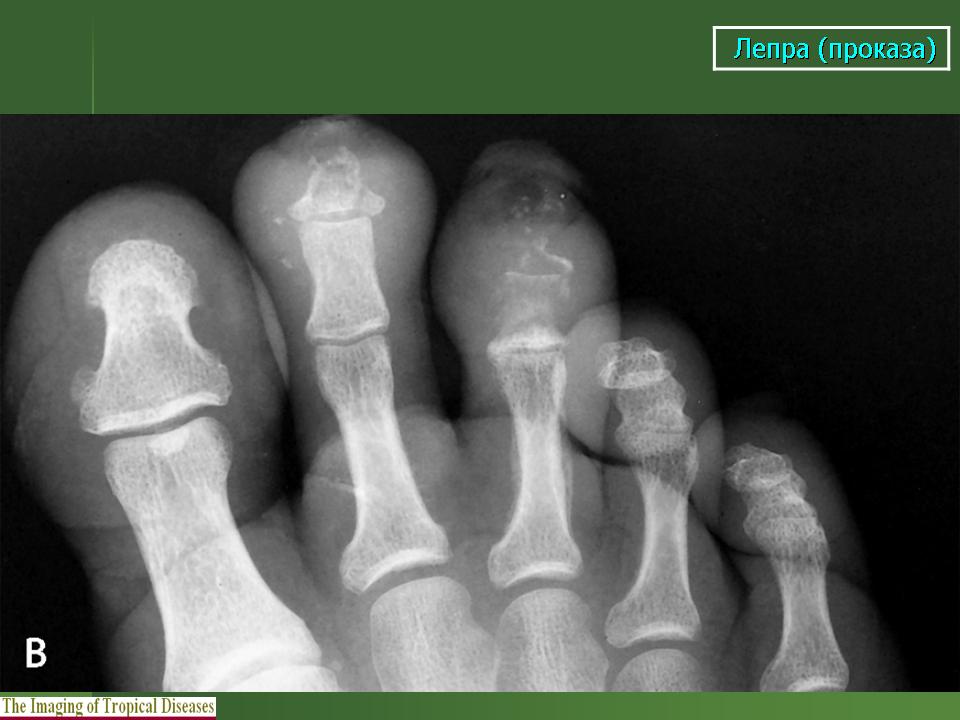

Что касается нервной формы проказы (рис. 216), то наиболее ранним, постоянным и общим рентгенологическим ее проявлением служит остеопороз. IK остеопорозу рано присоединяются явления остеолиза. Иконография (т. е. описание картины) остеолиза дается различными авторами в традиционном для лепрологии стиле в чрезвычайно тонких и кропотливых внешне описательных образах. Здесь преобладают сравнения с общеизвестными предметами, как, например, отточенными кончиками карандаша, шахматными пешками и другими фигурами, кнопками, пуговицами для воротника, запонками, тающими свечами, обсосанными леденцами, столбиками, иглами и т. д. Существенно то, что налицо частичное или полное рассасывание и исчезновение костных элементов без их замещения другой тканью и без продуктивной репаративной реакции. Характерно истончение и укорочение костей, в первую очередь ногтевых фаланг. Рассасывание ногтевой фаланги начинается с ее ногтевого отростка. Структура бугорка становится крупнопористой, ноздреватой. Затем срезается дистальный или боковой край, развивается плоская или вогнутая узура, постепенно увеличивающаяся, а затем и весь ногтевой отросток сходит на нет; обнажается шейка. Основание фаланги рассасывается с одного края или с обеих сторон, иногда и целиком. В дальнейшем без каких-нибудь клинических признаков очередь доходит до фаланг средних и основных, а также пястных и плюсневых костей, с переходом на запястье и предплюсну, порой до полного исчезновения скелета одного, нескольких, многих или всех пальцев.

В локализации этих костных поражений трудно определить какую-нибудь иннервационную закономерность, т. е. связь с тем или иным иннервационным районом, что свойственно всем костным поражениям "а нервнотрофической почве. Если в одних случаях имеется симметричность поражений, то в подавляющем большинстве случаев удивляет именно асимметрия двусторонних поражений. Тяжесть калечения при нервной проказе не находится в прямой связи с длительностью забдлевания.

Здесь также часто наступают нарушения целости костей -- истинные патологические переломы, без периостальной активности, без заживления костной мозолью. Переломы ускоряют рассасывание костей. Их не следует смешивать рентгенологически с костными дефектами на протяжении метафиза или диафиза кости. Иногда исчезновение костной ткани происходит сильнее проксимально, чем дистально, и отдельные костные участки могут "повиснуть" в мягких тканях. Отсюда они отходят, отторгаются наружу наподобие секвестров при костном панариции; трудно сказать, в какой мере здесь играет роль совсем необязательная вторичная инфекция, крайне вялая, если она действительно имеет место. Иногда развиваются истинные неврогенные остеоартропатии - лепрозные остеоартро-патии.

Вместе с тем при нервной лепре наблюдаются также настоящие костные анкилозы. Чаще всего это происходит в области плюсне-пред-плюсневых суставов, а между суставами малых трубчатых костей кистей и стоп анкилозы при проказе не развиваются. Калечения усугубляются еще тягой мышц. Происходит уклонение фаланг в стороны, большие расхождения суставных концов, крайние деформации. Мы наблюдали и лоозеровекие зоны перестройки костей на обычных и особенно необычных местах, с нормальным или извращенным их течением и исходом.